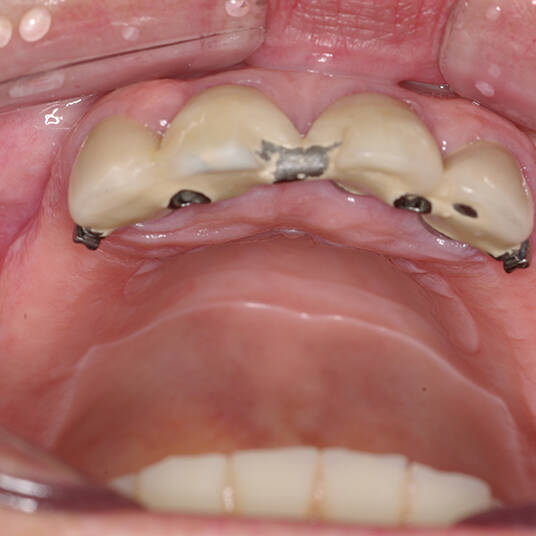

A Carga Imediata é uma técnica odontológica avançada que permite a colocação de uma prótese dentária fixa logo após a cirurgia de instalação dos implantes ou em poucos dias. Isso elimina a espera tradicional de meses para a integração completa do implante ao osso, oferecendo uma solução rápida e segura para restaurar dentes perdidos.

- Fixação da Prótese: Em até 72 horas após a cirurgia, a prótese provisória é instalada, permitindo que o paciente recupere a funcionalidade e a estética imediatamente.